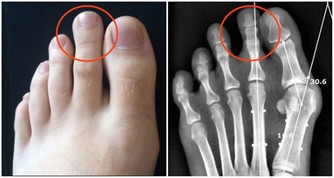

維生素C,0.6克會出現尿頻,超過1克可使皮膚發紅,增強腸蠕動,引起腹部絞痛、腹瀉。服用維生素C 4~12克,可使尿酸鹽在尿道中沉澱形成結石。